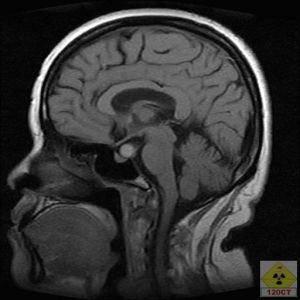

顱腦CT檢查 顱腦的CT檢查是通過CT對顱腦進行檢查的一種方法。頭顱CT是一種檢查方便,迅速安全,無痛苦,無創傷的新的檢查方法,它能清楚的顯示顱腦不同橫斷面的解剖關係和具體的腦組織結構。因而大大提高了病變的檢出率和診斷的準確性。總體上講,CT對人體硬組織的顯像要比軟組織的更好。頭顱CT檢查對於顱內、顱骨、頭皮的大部分疾病的診斷有重要意義(包括外傷、腫瘤、炎症、血管病變、中毒、變性和代謝性疾病等)。

(4)腦CT掃描發現膿腫、乳突X線攝片顯示骨質破壞或膽脂瘤。